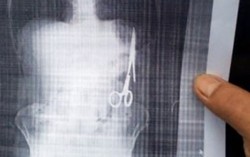

Chiếc kéo dài gần 1 gang tay nằm trong bụng 18 năm

Phòng & chữa bệnh 12:12 28/12/2016Sau 18 năm phẫu thuật, thời gian gần đây, ông Ma Văn Nhật, sinh năm 1962, ở huyện Chợ Đồn, tỉnh Bắc Kạn, đi kiểm tra sức khỏe thì được phát hiện chiếc kéo dài 15cm nằm trong ổ bụng.